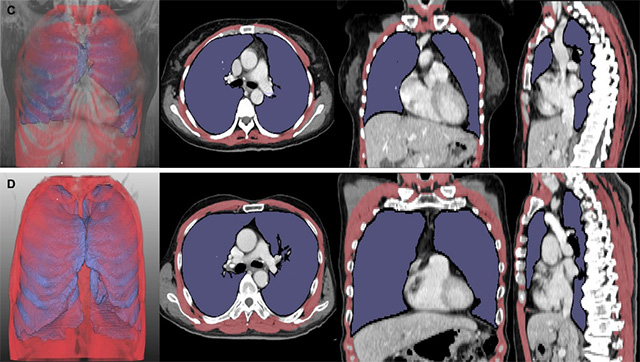

• 루게릭병 환자의 흉부 CT 분석 결과. 폐 용적 지수(LVI, 보라색)와 호흡근 용적 지수(RMI, 빨간색)가 낮은 환자는 높은 환자보다 생존 기간(위 5개월 vs 아래 43개월)이 짧았다. /사진 제공=서울대병원

▲ 루게릭병 환자의 흉부 CT 분석 결과. 폐 용적 지수(LVI, 보라색)와 호흡근 용적 지수(RMI, 빨간색)가 낮은 환자는 높은 환자보다 생존 기간(위 5개월 vs 아래 43개월)이 짧았다. /사진 제공=서울대병원

연구팀은 루게릭병 환자의 CT 영상에서 폐와 호흡근의 용적 지수를 정량화한 새로운 지표를 개발했다. 구체적으로, 폐 용적 지수(LVI)와 호흡근 용적 지수(RMI)를 산출해 병기 및 생존 기간과의 상관관계를 분석했다. 두 지수는 폐와 호흡근 부피(㎤)를 키의 제곱(㎡)으로 나눈 값이다.

분석 결과, LVI와 RMI는 병기가 증가할수록 유의하게 감소했으며, 두 지수가 낮은 환자군은 기관절개술이나 사망에 이르는 시점이 상대적으로 빨랐다. 통계 분석에서도 이 지수들은 기존 폐활량 검사와 유사한 정확도로 예후 평가에 활용될 수 있음을 확인했다. 특히 구음장애 환자군에서도 일관된 결과가 도출돼, 영상 기반 지표가 기존 검사의 한계를 보완할 수 있는 가능성을 보여줬다.